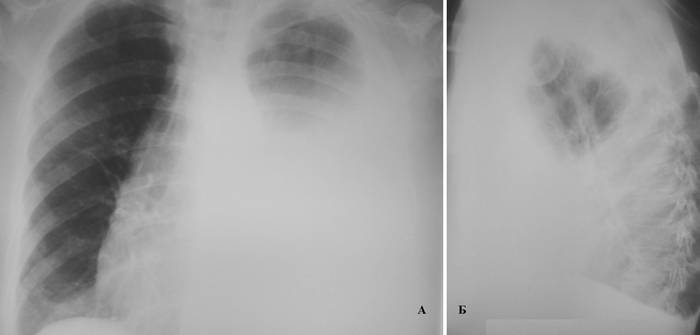

ДИСКОВИДНЫЙ АТЕЛЕКТАЗ ЯЗЫЧКОВЫХ СЕГМЕНТОВ ЛЕВОГО ЛЕГКОГО.

25.11.2015 — КТ грудного отдела с контрастированием:

Слева дисковидный ателектаз язычковых сегментов легкого.

Очаговых, инфильтративных изменений легких не выявлено. Корни структурны. Легочный рисунок не изменен. Диафрагма расположена обычно. Просветы трахеи, главных, долевых, сегментарных бронхов сохранены. Средостенение не расширено, не смешено. Увеличения лимфатических узлов средостения и корней лёгких не отмечено. Надключичные, подмышнчные лимфоузлы не увеличены. Плевра не изменена. Границы сердца не расширены. В полости перикарда выпот не определяется. Лёгочные артерии контрастируются равномерно. Мягкие ткани грудной клетки не изменены. Костных деструктивных изменений не выявлено.

Зпаключение: очагов неопластического процесса в органах грудной полости не выявлено.